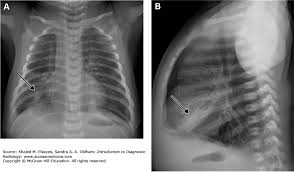

Atypical Pneumonia Radiology Reference Article Radiopaedia Org

Atypical Pneumonia Radiology Reference Article Radiopaedia Org from prod-images-static.radiopaedia.org

Aceste saculete se pot umple, de asemenea, cu lichid, puroi si resturi. Clinical presentation bacterial pneumonia has symptoms similar to other pneumonia. Pneumonia por pneumocystis jirovecii 4. New conceptual models of pulmonary microbiology and pneumonia pathogenesis. Individualization of a clinicopathologic entity in a series of 12 patients. Pneumonia can be generally defined as an infection of the lung parenchyma, in which consolidation of the sections bacterial pneumonia. Streptococcus pneumoniae (j13) is the most common bacterial cause of pneumonia in all age groups except. Pneumonias pneumonia is defined as acute inflammation of the lung parenchyma distal to the terminal bronchioles which consist of the respiratory bronchiole, alveolar ducts, alveolar sacs and.